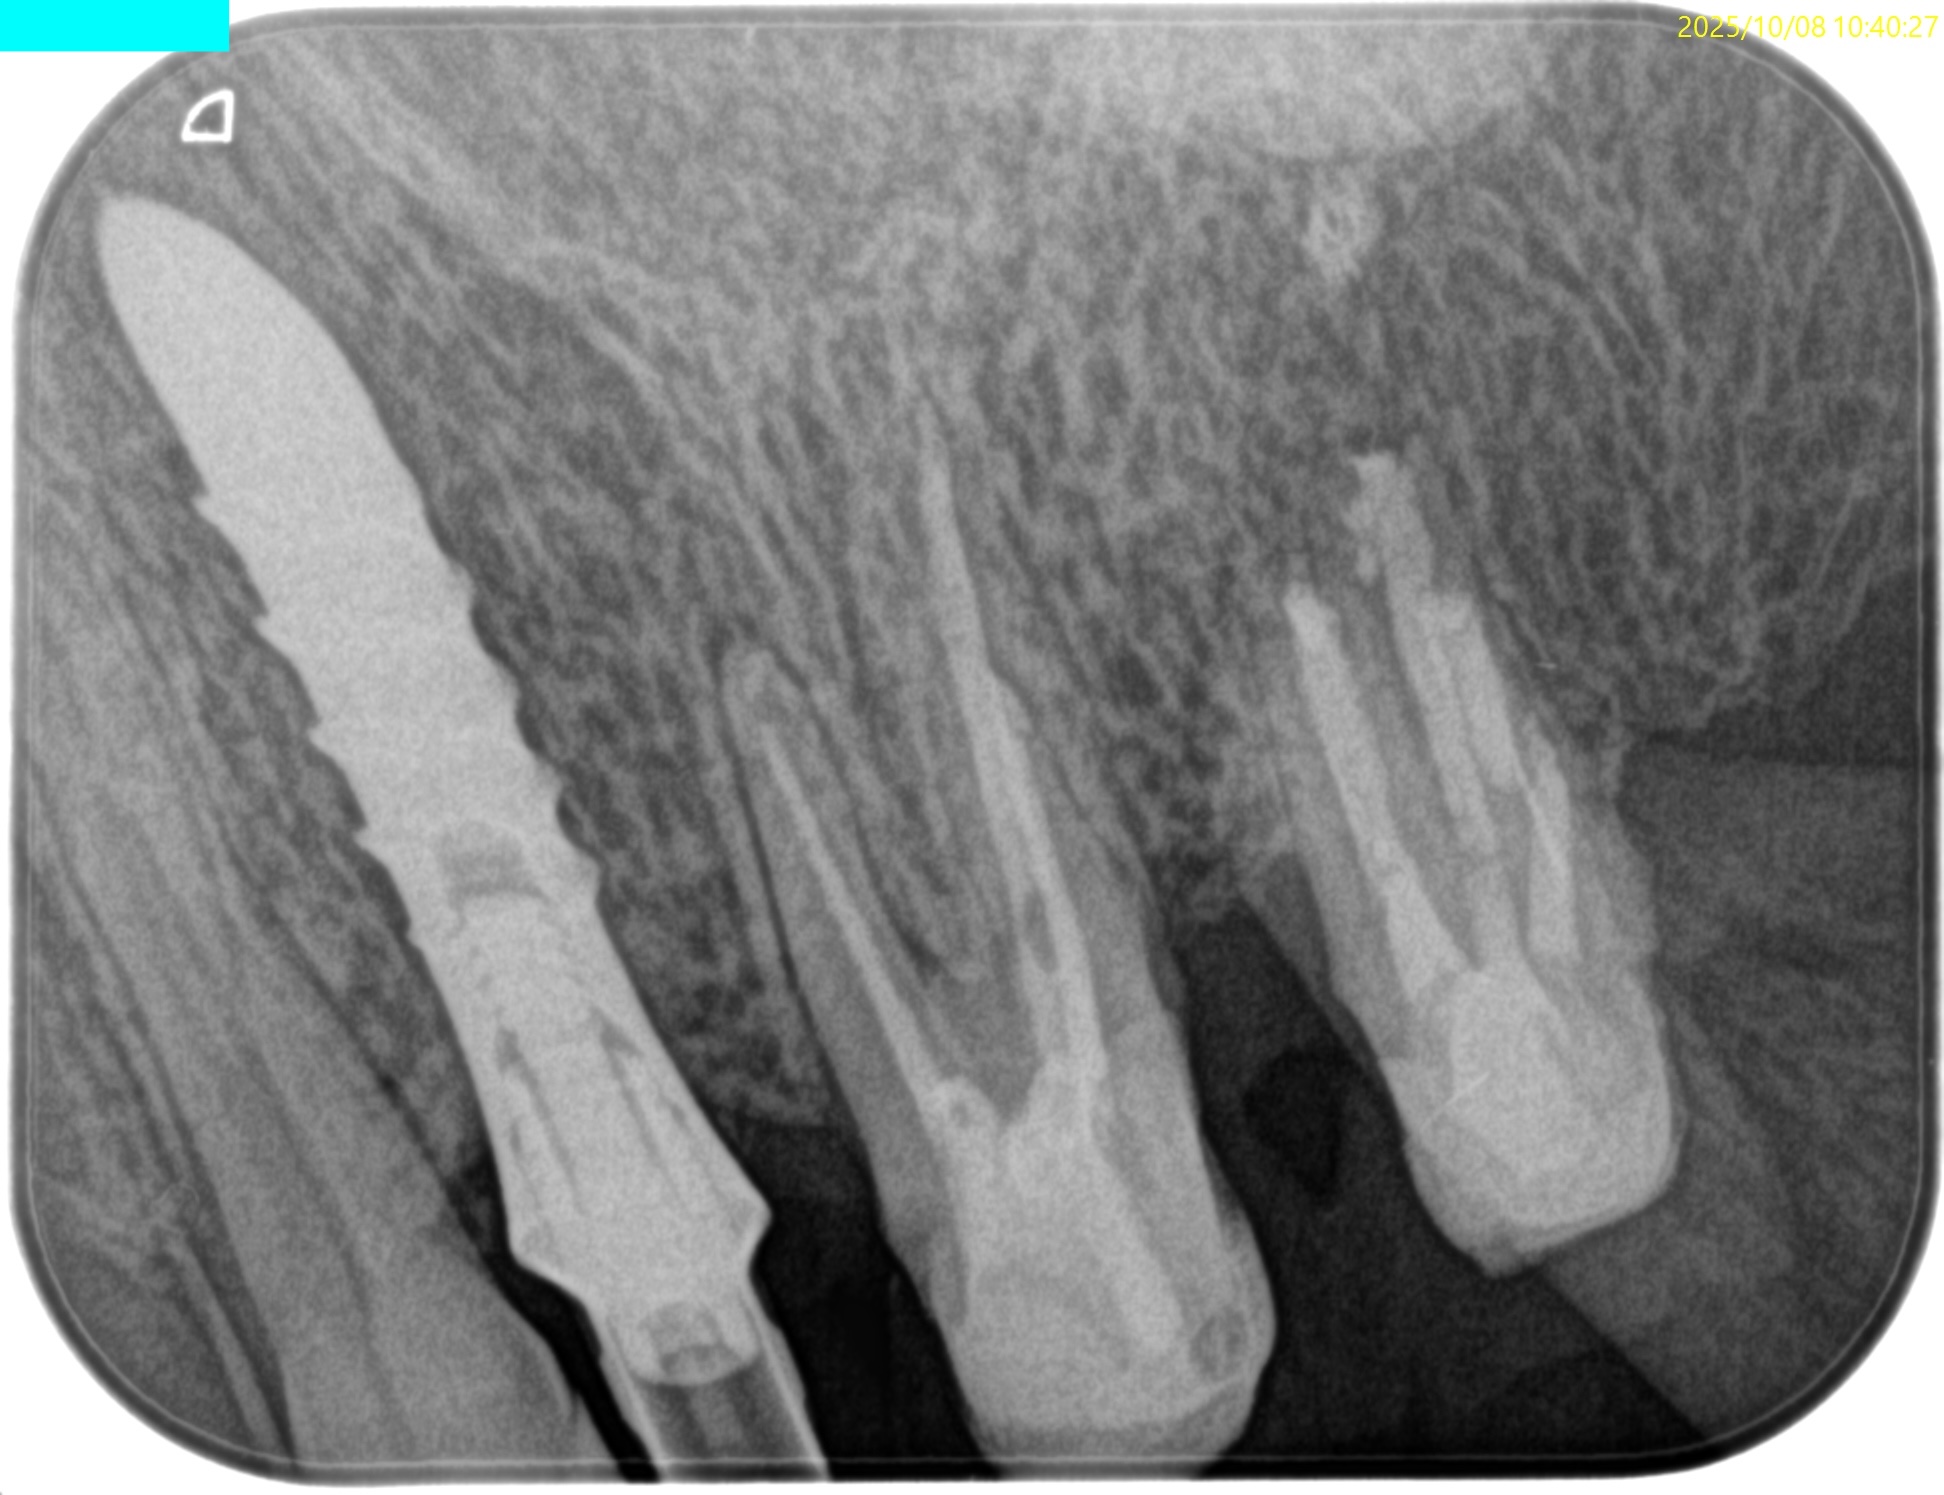

#15 Intentional Replantation 6M recall(2025.10.8)

#15 MB

#15 DB

#15 P

治療直後と比較した。

歯槽骨の改善が大幅にみられた。